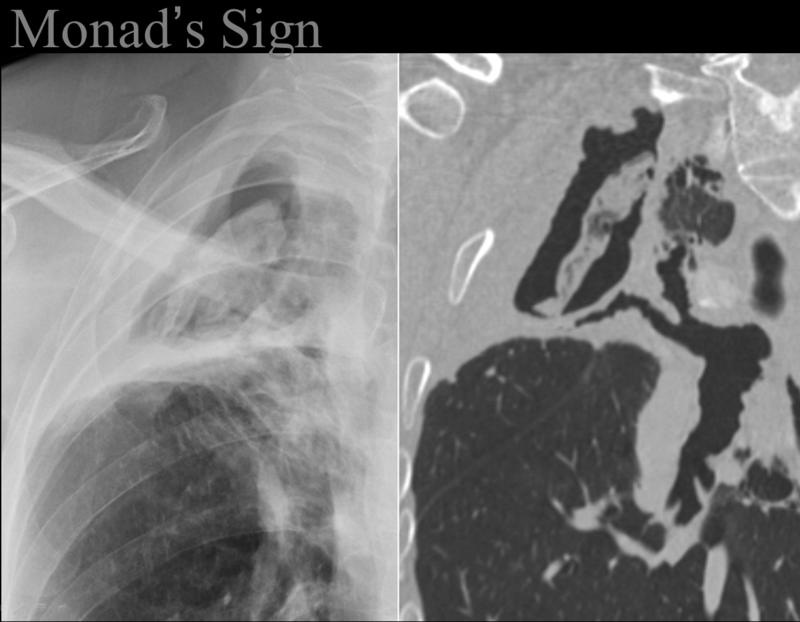

Monad's sign

Aspergilloma